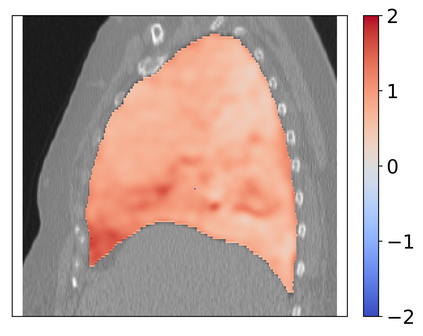

Deformable image registration is a fundamental task in medical image analysis and plays a crucial role in a wide range of clinical applications. Recently, deep learning-based approaches have been widely studied for deformable medical image registration and achieved promising results. However, existing deep learning image registration techniques do not theoretically guarantee topology-preserving transformations. This is a key property to preserve anatomical structures and achieve plausible transformations that can be used in real clinical settings. We propose a novel framework for deformable image registration. Firstly, we introduce a novel regulariser based on conformal-invariant properties in a nonlinear elasticity setting. Our regulariser enforces the deformation field to be smooth, invertible and orientation-preserving. More importantly, we strictly guarantee topology preservation yielding to a clinical meaningful registration. Secondly, we boost the performance of our regulariser through coordinate MLPs, where one can view the to-be-registered images as continuously differentiable entities. We demonstrate, through numerical and visual experiments, that our framework is able to outperform current techniques for image registration.